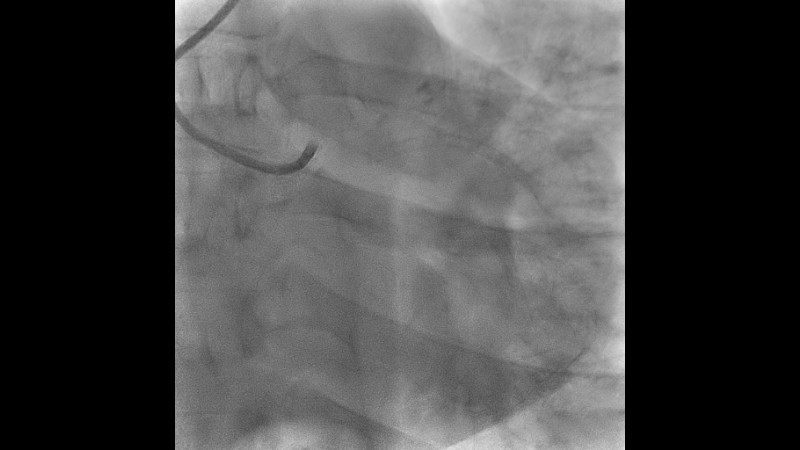

Explore the management of heavily calcified LAD lesions in this PCRGulf-GIM 2025 session. Discover how OCT imaging guides lesion assessment, differentiates superficial from deep calcium, and informs the need for plaque modification. Learn when and how to use orbital atherectomy or intravascular lithotripsy, and follow the step-by-step stent implantation, optimisation, and final evaluation using both angiography and OCT.

- To learn indications of calcium modification using orbital atherectomy or other modalities, based on findings on OCT images.